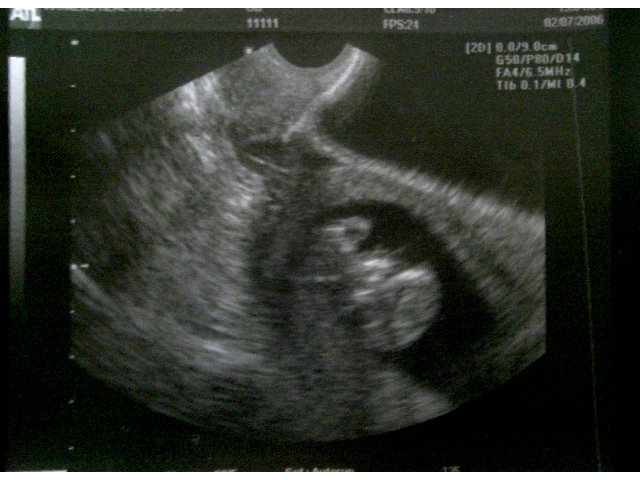

Spike at 10 weeks